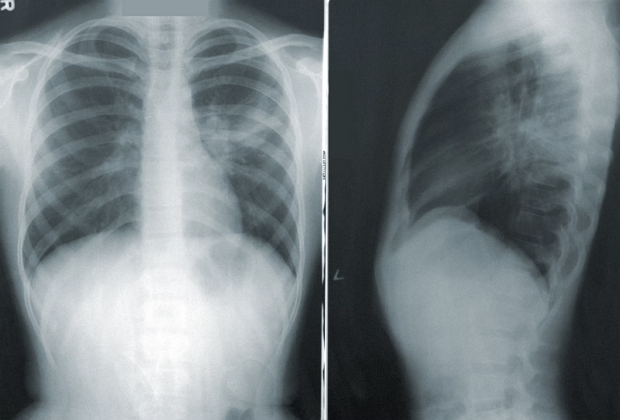

폐렴의 초기 증상을 알아차리는 것은 적절한 치료를 받고 합병증을 예방하는 데 매우 중요합니다. 대표적인 초기 증상으로는 지속적인 기침, 호흡곤란, 가슴 통증, 그리고 발열이 있습니다. 이러한 증상은 때때로 감기나 독감과 혼동될 수 있으나, 폐렴의 경우 일반적인 감기보다 더 심각한 문제로 발전할 수 있기 때문에 주의 깊게 관찰하는 것이 중요합니다.

폐렴의 초기 증상은 개인에 따라 다를 수 있으며, 특히 노인이나 면역 체계가 약한 사람들은 더욱 심각한 증상을 경험할 수 있습니다. 폐렴은 종종 고열, 심한 기침과 더불어 누런 색의 가래를 동반하며, 이러한 증상들은 폐의 염증과 감염을 나타냅니다.